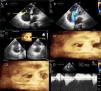

Foi submetida a exame de ecocardiograma transtorácico, em que se realizaram imagens com recurso a ecocardiografia tridimensional (Figs. 2 e 3).

Envolvimento carcinóide da válvula tricúspide. A – Apical 4 câmaras, em sístole, que revela dilatação das cavidades direitas, com folhetos da válvula tricúspide espessados, que não coaptam, em posição semiaberta. B – Doppler-cor demonstrando insuficiência tricúspide grave. C – Pormenor em ecocardiografia tridimensional, com comparação das válvulas tricúspide e mitral, observado da face ventricular. C1 – Pormenor de ecocardiografia tridimensional, em diástole, mostrando folhetos da válvula tricúspide fixos, imóveis, espessados quando comparados com os folhetos da válvula mitral. C2 – Pormenor de ecocardiografia tridimensional, em sístole, revelando o encerramento da válvula mitral e o não encerramento da válvula tricúspide. D – Doppler contínuo que revela a insuficiência tricúspide. VT – Válvula tricúspide; VM – Válvula mitral.

Envolvimento carcinóide da válvula pulmonar. A – Trato de saída do ventrículo direito. Folhetos da válvula pulmonar espessados. B – Doppler-cor que mostra fluxo diastólico ligeiramente turbulento de insuficiência pulmonar ligeira. C – Doppler contínuo que revela estenose pulmonar ligeira. RVOT – trato de saída do ventrículo direito; VP – Válvula pulmonar.

O ecocardiograma transtorácico revelou dimensões normais do ventrículo esquerdo e espessura das paredes normais, sem alterações segmentares da contratilidade, com função sistólica global conservada. As cavidades direitas estavam dilatadas (Fig. 2-A), com boa função sistólica global do ventrículo direito (tricuspid annular plane systolic excursion de 22mm), não se detetando gradiente significativo entre o ventrículo direito e a aurícula direita (Fig. 2-D). Era possível observar o espessamento dos folhetos da válvula tricúspide, que não coaptam em sístole, condicionando insuficiência tricúspide grave (Fig. 2-B), pormenor este mais evidente nas imagens de ecocardiografia transtorácica tridimensional (Figuras 2-C1 e 2-C2).

A válvula pulmonar apresentava cúspides espessadas, condicionando estenose pulmonar ligeira (Fig. 3-C) e insuficiência pulmonar também ligeira (Fig. 3-B).